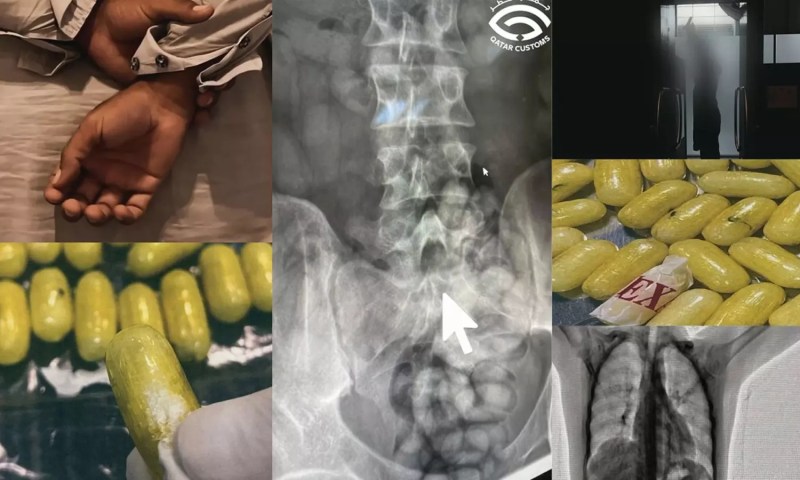

ശരീരത്തിനുള്ളിൽ ലഹരിമരുന്ന് ഒളിപ്പിച്ച യാത്രക്കാരൻ ഖത്തറില് പിടിയിൽ

ദോഹ: ഖത്തറിൽ ശരീരത്തിനുള്ളിൽ ലഹരിമരുന്ന് ഒളിപ്പിച്ച യാത്രക്കാരൻ പിടിയിൽ. ഹമദ് അന്താരാഷ്ട്ര വിമാനത്താവളത്തിൽ വെച്ചാണ് ലഹരിമരുന്ന് വിഴുങ്ങിയെത്തിയ യാത്രക്കാരൻ പിടിയിലായത്.passenger

ലഹരിമരുന്ന് ക്യാപ്സൂളുകളുടെ രൂപത്തിലാക്കി വിഴുങ്ങിയാണ് ശരീരത്തിനുള്ളിൽ ഒളിപ്പിച്ചത്. സംശയത്തെ തുടർന്ന് യാത്രക്കാരനെ ബോഡി സ്കാനർ പരിശോധനക്ക് വിധേയമാക്കുകയായിരുന്നു. കൂടുതൽ ചോദ്യം ചെയ്യലിനെത്തുടർന്ന് വൈദ്യപരിശോധനക്ക് വിധേയമാക്കിയപ്പോൾ കുടലിൽനിന്ന് 80-ഓളം നിരോധിത ഗുളികകൾ കണ്ടെത്തി. 610 ഗ്രാം വരുന്ന ഷാബുവും ഹെറോയിനുമാണ് അധികൃതർ പിടിച്ചെടുത്തത്. വിഡിയോ ദൃശ്യങ്ങൾ കസ്റ്റംസ് വിഭാഗം സമൂഹ മാധ്യമങ്ങളിൽ പങ്കുവെച്ചു.